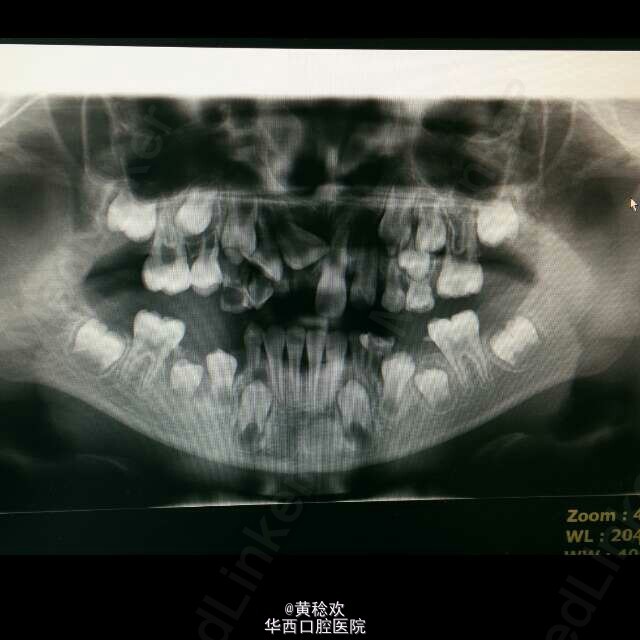

乳牙早失的小反合

今天跟着老板看初诊,来了一个反合的小病人,面型较凹,下前牙已换,上前牙AI,II和BII滞留,反覆合大,但是患者嘴里乳牙几乎全为残根残冠,几乎不可能提供什么支抗,请问一下大家,这个病人现阶段能做什么处理,还是说就等着成年后手术呢?